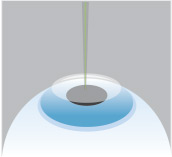

Step 3

An excimer laser is then used to precisely reshape the curvature of the cornea’s surface.